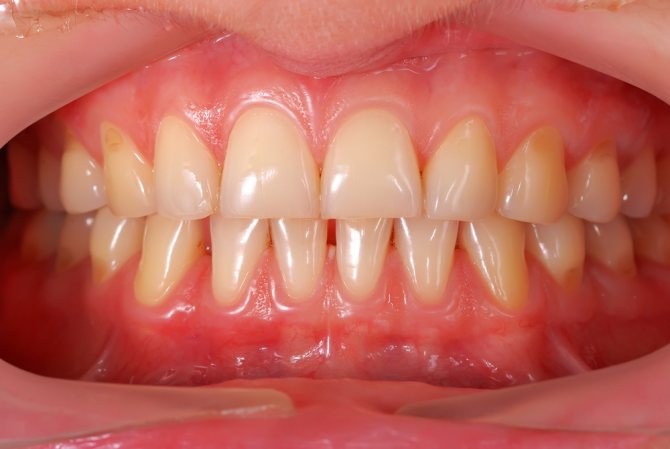

- Кандидозный стоматит или молочница ротовой полости — одно из основных заболеваний, при котором во рту появляются белые пятна и налет. Его появление чаще всего бывает связано с ослаблением иммунитета, благодаря чему его возбудитель — грибок Candida — начинает активно размножаться в полости рта. Белые пятна в этом случае напоминают творожистый налет, обильно покрывающий слизистую. При попытках его устранить обнажаются многочисленные очаги воспаления, а в последствии и эрозии.

Белый налет может возникнуть на любом участке рта. Высыпания имеют творожистую структуру. При развитии заболевания у взрослого появляются плохие ощущения. Клинические признаки патологии зависят от индивидуальных особенностей организма, а также от характера течения болезни. Большинство пациентов жалуются на сухость во рту, проблемы с глотанием, чувство зуда и жжения. Токсические вещества, выделяемые в результате активности грибковых бактерий, ухудшают общее самочувствие больного.

Молочница в ряде случаев сопровождается воспалительным процессом каймы губ. Степень развития воспаления определяется состоянием иммунной системы. Главный клинический признак молочницы – образование белого налета во рту. При своевременном лечении удастся быстро избавиться от неприятной симптоматики и патогенных микроорганизмов.